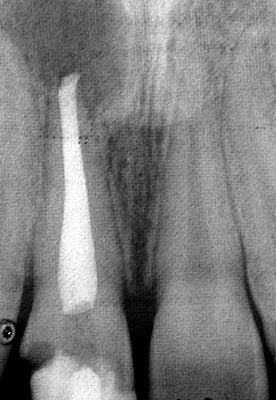

How root canal treatment can help

The purpose of root canal treatment is to remove the inflamed tissue or bacteria inside the root canal and thus allow the surrounding tissues to heal.